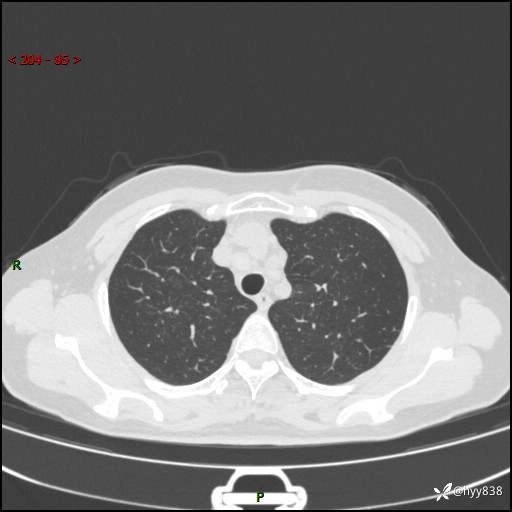

【患者信息】:58岁/女

【主诉】:体检发现肺结节

【检查】:胸部CT平扫+增强